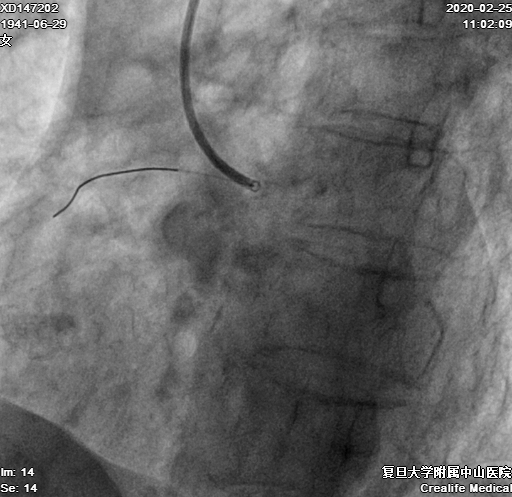

换用4F Transporta GE成功送至右冠中段(图7)

图7